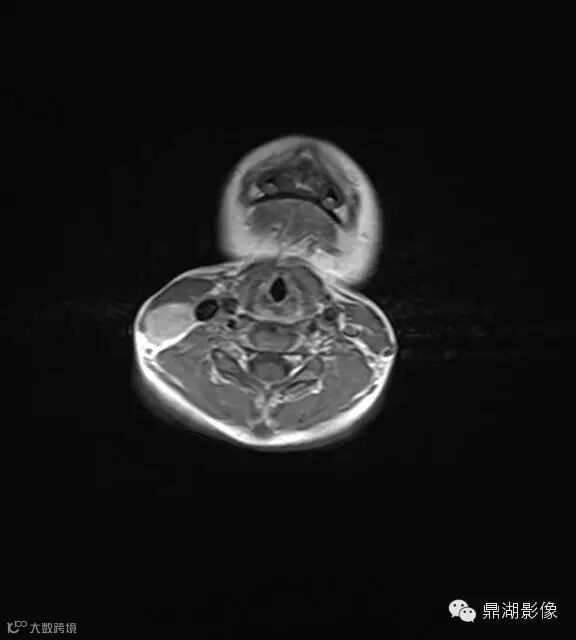

上海儿童医院韩燕乔教授诊断:考虑淋巴结炎 ,可见杯状分层,液液平

神经源性肿瘤:肿块较大,信号常不均,有人认为肿瘤位于屈肌的区域或伴有肌肉萎缩强烈提示神经源性肿瘤。

淋巴结核:多融合成团,呈花环状,边缘强化,淋巴结内见到斑点状钙化有助结核的诊断。

猫抓病性淋巴结炎:不少医生诊断为猫爪病,该病确实很接近。均为炎性改变,脓肿、坏死形成时,虽呈边缘强化特点,但多个淋巴结间界限清楚,无融合改变,内也无斑点状钙化。